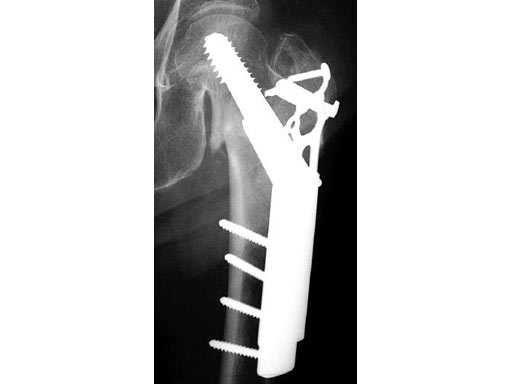

Locking Trochanter Stabilization Plate

The Locking Trochanter Stabilization Plate is intended for the treatment of unstable pertrochanteric fractures in combination with the Dynamic Hip Screw (DHS), especially for 4-part fractures with greater trochanter.

Using the plate limits the possibility of varus deformation of the proximal fragment by cutting out the screws and medialization of the distal femoral fragment, without impairing the function and dynamization capacity of the DHS. The Locking Trochanter Stabilization Plate limits diaphyseal medialization by fastening onto the greater trochanter relief. The additional proximal internal fixaton can be achieved by using 3.5 mm locking head screws.

79-year-old woman.